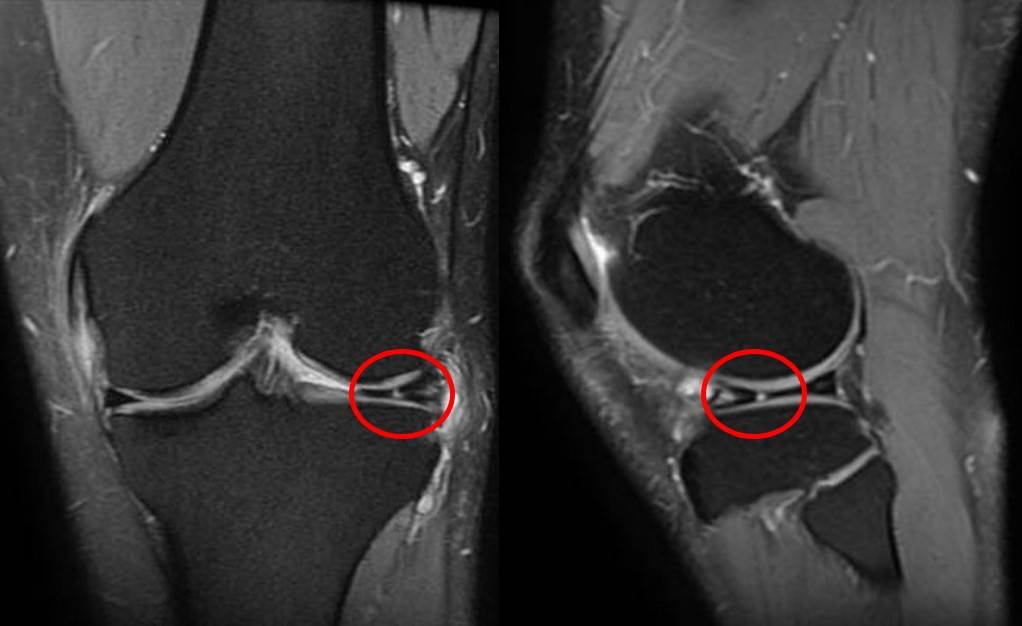

Para visualizar o menisco com precisão, o exame de referência é a ressonância magnética. A ressonância magnética do joelho permite identificar a extensão da ruptura, o grau de deslocamento da alça e a qualidade do tecido meniscal.

Em situações de travamento agudo com bloqueio evidente ao exame físico, a indicação pode ser mais direta. Mas, em geral, a ressonância é o caminho para confirmar o diagnóstico e afastar lesões associadas, como danos à cartilagem ou ao ligamento cruzado anterior. A decisão sobre solicitar ou não o exame depende sempre da avaliação clínica individualizada.